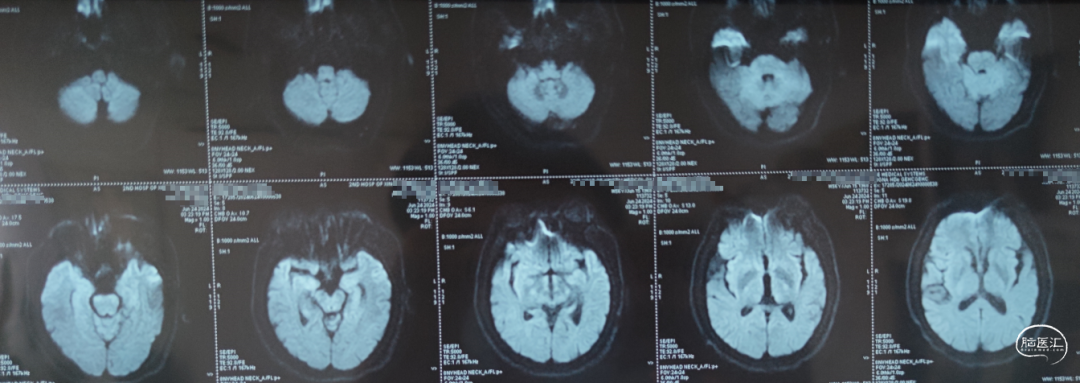

头颅MRI:未见新鲜脑梗死

DWI:

第二次住院,夜间再发头晕、呕吐、视物重影,约10分钟后好转。次日早晨来院,入院查体未见阳性体征,行急诊头颅MRI+DWI:未见急性梗死病灶。